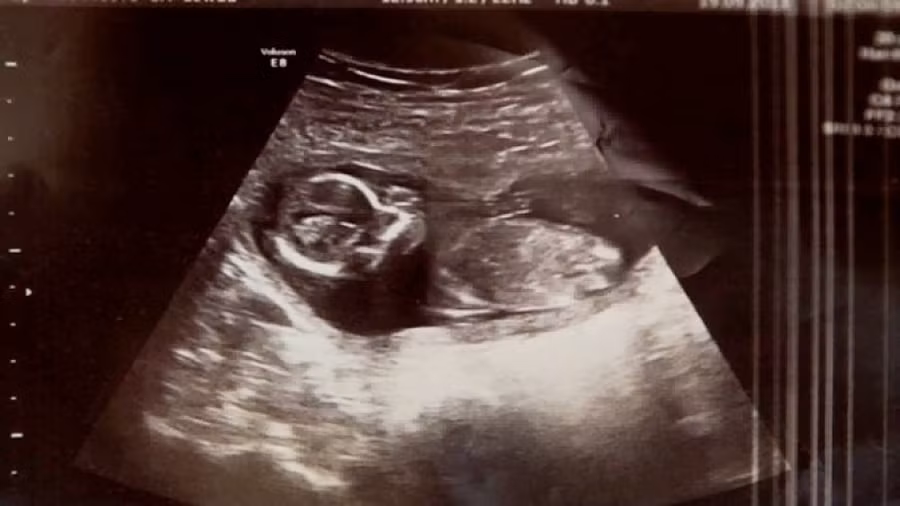

Các bác sĩ tại bệnh viện Rotunda, Dublin đã kiểm tra Michelle một lần cuối trước khi nạo vét và phát hiện nhịp tim đập ngay trong tử cung của bà mẹ – Michelle vẫn đang mang thai!…

“Không thể tin được, chúng ta có nhịp tim đập“, vị bác sĩ trẻ bối rối giải thích với một đồng nghiệp già hơn vừa được gọi tới. Hạnh phúc lại mỉm cười với Michelle một lần nữa.

Hóa ra, bà mẹ Michelle đã mang thai song sinh, và cô mới chỉ mất có một đứa trẻ. Đứa trẻ còn lại đã bị che khuất bởi máu và dịch do vụ sảy thai, khiến cho các bác sĩ không thể xác định được em trong quá trình siêu âm.